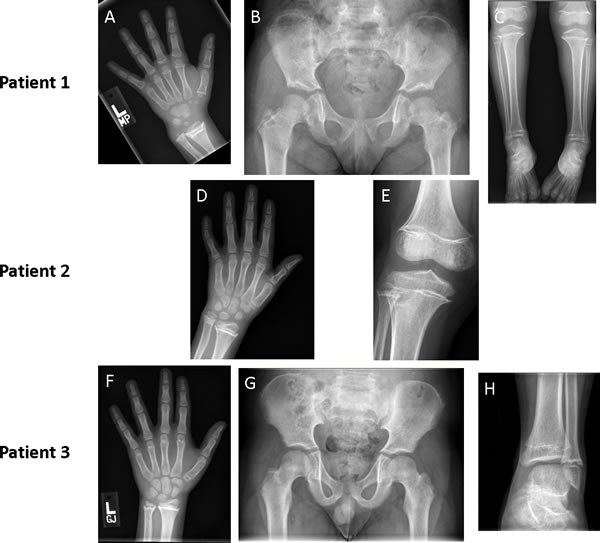

Figure 2: Imaging of patients at follow up showing skeletal deformities resulting from widespread physeal fusions. Radiographs of patient 1 at 18 months after cessation of therapy show protrusion of the ulnar head and widespread physeal fusion in hand bones (Panel A); abnormally short femoral necks (Panel B); and varus ankles, with widespread physeal fusions of bones in the lower leg (Panel C). Radiographs of patient 2 at 14 months after completion of vismodegib therapy show widespread physeal fusions in hand and forearm bones (Panel D) accompanied by sclerotic thickening in all physes of the knee (Panel E). Three radiographs of patient 3 taken 16 months after cessation of therapy show abnormalities that are less prominent but similar to those of patient 1. Advanced bone age (Panel F), shortened femoral necks (Panel G), and distal fusion of the tibia with relative sparing of the fibula (Panel H) was seen.

Over time, effects of physeal fusions have become more evident. Although short stature may in part be attributable to prolonged therapy, her height, which was at the 43rd percentile at 36 months of age, dropped to less than 3rd percentile by 60 months of age (Table 1). Bony protrusions have developed around her wrists, ankles, and knees. Her hands exhibit mild radial deviation around the wrist, with notable projection of the ulnar head. Her ankles demonstrate varus deformity, with the lateral malleolus appearing to overhang the normal position. Prominent fibular heads can be palpated around lateral aspects of her knees. Radiography of bones and joints show widespread systemic physeal fusions with increased metaphyseal sclerosis in phalanges of hands and feet, proximal humeri, distal radii, proximal and distal tibiae, femora, and fibulae (Figure 2). Despite this widespread distribution, all physes are not equally involved and presence of incomplete fusions, alongside complete ones, raise concern that disproportionate bone growth might eventually restrict her ability to walk and use hands normally.

Two years after stopping vismodegib, her height has gone from the 83rd percentile at 5 years to the 8th percentile at 8 years. In addition, her bone age has advanced 6 years beyond her chronologic age to 14 years (Table 1 and Figure 2).

Currently, 19 months after stopping vismodegib, his height has gone from the 70th percentile at 6 years to less than the 10th percentile at 9 years (Table 1). Skeletal survey revealed widespread partial and complete physeal fusions similar to those in patient 1 (Figure 2).

Indeed, here we describe 3 cases of growth plate fusions in patients on vismodegib and a very recent publication also describes 3 additional cases seen in patients receiving the Hh inhibitor, sonidegib (LDE225). [15] These 6 cases clearly show that disruption of the Hh pathway through SMO antagonism can affect developing humans in a similar manner as developing mice. In mice, exposure to SMO inhibitor resulted in blocked proliferation and early differentiation of chondrocytes, followed by a marked increase in mineralization within the growth plate once the agent was withdrawn; [6] a process that bears eerie resemblance to what has been described in these 3 cases. For the mice, the end result was the shortening of bones and dysplastic joint formation that drew parallels to signs associated with IHH deficiency. [6] Intriguingly, some of the growth abnormalities observed, particularly in Patients 1 and 3 (Figure 2), are also akin to those in patients born with IHH deficiency, which causes the autosomal recessive syndrome acrocapitofemoral dysplasia that is characterized by short-limb dwarfism and brachydactyly. [16]